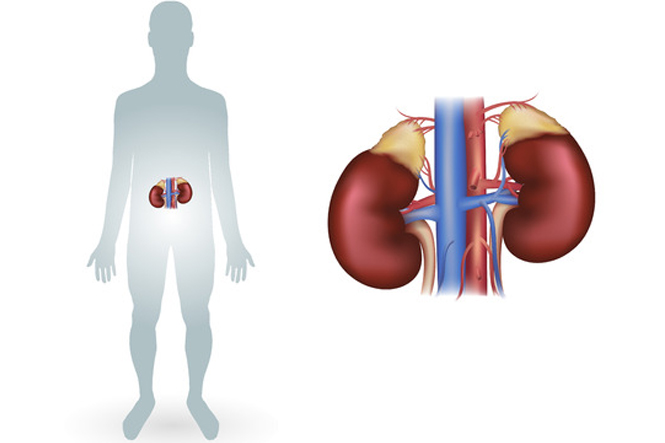

Your kidneys have a key role in your health. They filter and remove waste and excess fluid from your body. This means you need to take good care of them. Find out how to look after your kidneys, the signs they're not functioning well and more.